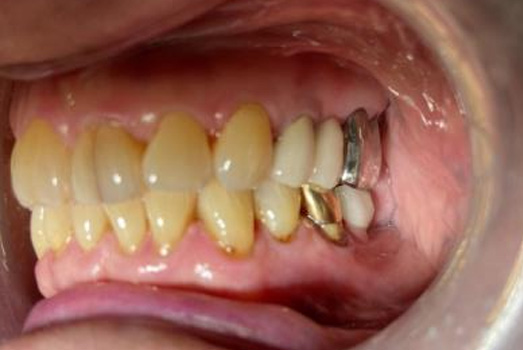

Final Intraoral Photographs